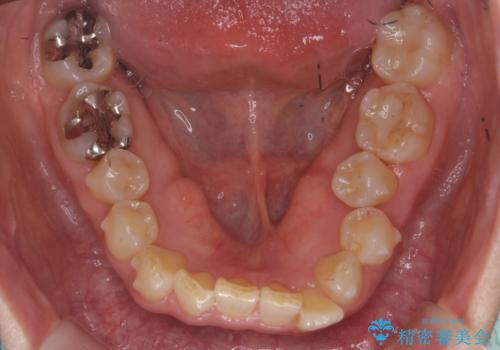

50代女性 インビザライン かみ合わせが深く、難しい症例

かみ合わせが深く、上の歯が咬みこんで下の歯にワイヤーがつけられない状態で、ワイヤー矯正はかなり難しい状態でした。

反対咬合や、すれ違い咬合もあり、大変難しいケースでしたが治療することができました。

かみ合わせが深い方はもともとかみしめが強く、マウスピース矯正を長期にすると、奥歯が咬まなくなってくる症状が強くなります。

今回もそういった状態になったのを、装着時間や歯の移動を工夫する形で治療しました。